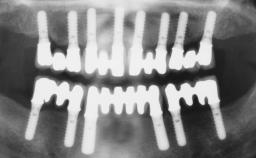

A 63-year-old male patient was referred for a consultation and treatment of partial edentulism in the maxilla. The patient presented with residual anterior teeth and declined a partial removable prosthesis. He reported that the maxillary posterior teeth had been extracted due to mobility and periodontal disease two months before the consultation. The patient’s chief complaint was that his residual maxillary teeth were mobile and that he was unable to chew. The patient’s desire was a stable and comfortable fixed maxillary rehabilitation. The patient was a light smoker (fewer than 10 cigarettes/ day), and his medical history was without significant findings. He was not on any regular medication at the time of consultation. The extraoral examination revealed a normal physiognomy with a correct distribution of the facial thirds. The patient presented a low lip line, and the transition line between teeth and soft tissues was not exposed during a forced smile.